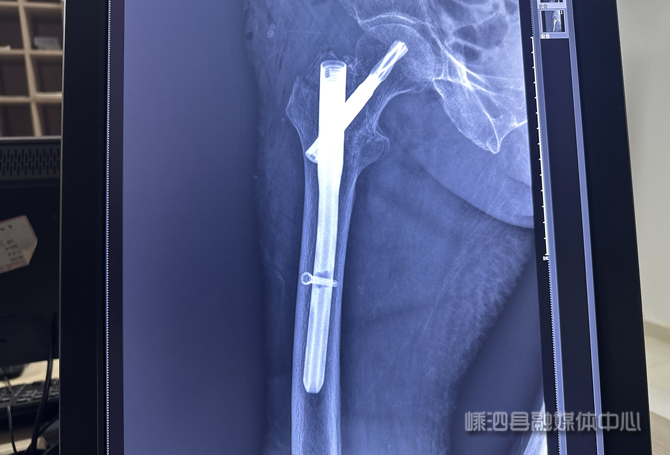

据了解,患者邵女士因意外摔倒导致右侧股骨粗隆间骨折,同时伴有老年性骨质疏松、中度贫血、低蛋白血症等多种基础疾病,手术风险较高。面对高龄患者,浙江医院“山海提升”专家、副主任医师毛谡第一时间组织骨伤科、内科等科室进行术前风险评估,并制定手术方案。术中,团队采用闭合复位技术,通过精准的透视定位,置入髓内针进行固定,手术历时约一个小时,过程顺利。术后患者被转入ICU密切监护,24小时内生命体征平稳,未出现并发症。目前已转入普通病房进行后续治疗与康复。

股骨粗隆间骨折闭合复位髓内钉内固定术通过微创方式将髓内针植入股骨髓腔,实现骨折复位与固定,具有创伤小、出血少、恢复快的优势,尤其适合高龄患者。此次手术的成功实施,展现了县人民医院在“山海提升”工程帮扶下,骨科微创技术水平与多学科协作处理高龄、高危病例能力的显著提升。通过引进上级医院的先进技术与管理经验,让海岛居民在家门口就能享受到优质的医疗服务,切实解决了群众跨海就医的难题。